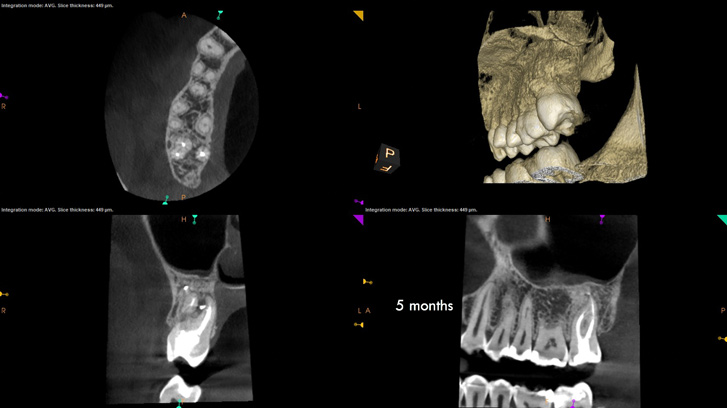

In the first case study, a young female patient was told she had a tooth (tooth No. 2, Figure 3) that should be extracted due to extensive bone loss. Using CBCT, the clinician was able to identify a large lateral canal within the palatal root. Despite the bone loss, the patient was eager to save her tooth. He offered to treat the tooth with the broad-spectrum acoustic technology. As shown in Figure 4, the preparation space was much smaller, which he was able to obturate efficiently. In addition, the small pinpoint of sealer in the middle of the palatal root indicated that the palatal lateral canal had been addressed (Figure 5). In the clinician's opinion, this area was likely the primary source of much of the bone loss.

Figure 6 through Figure 8 demonstrate that, 5 months after the procedure, complete healing had occurred, notably on the distal, where the probing had resolved to 2 mm. The patient then had a crown placed by her general dentist. Given her positive experience with the technology, she was eager to return as needed for continued follow-up.

Fig 3. Case 1: CBCT showed a large lateral canal within the palatal root (Fig 3). There was a small preparation space, which was efficiently obturated (Fig 4). A small pinpoint of sealer in the middle of the palatal root indicated that the palatal lateral canal had been addressed (Fig 5). After 5 months, CBCT demonstrated complete healing (Fig 6), notably on the distal, where probing had resolved to 2 mm. Radiographic images were taken immediately postoperatively (Fig 7) and 5 months postoperatively (Fig 8).

Fig 4. Case 1: CBCT showed a large lateral canal within the palatal root (Fig 3). There was a small preparation space, which was efficiently obturated (Fig 4). A small pinpoint of sealer in the middle of the palatal root indicated that the palatal lateral canal had been addressed (Fig 5). After 5 months, CBCT demonstrated complete healing (Fig 6), notably on the distal, where probing had resolved to 2 mm. Radiographic images were taken immediately postoperatively (Fig 7) and 5 months postoperatively (Fig 8).

Fig 5. Case 1: CBCT showed a large lateral canal within the palatal root (Fig 3). There was a small preparation space, which was efficiently obturated (Fig 4). A small pinpoint of sealer in the middle of the palatal root indicated that the palatal lateral canal had been addressed (Fig 5). After 5 months, CBCT demonstrated complete healing (Fig 6), notably on the distal, where probing had resolved to 2 mm. Radiographic images were taken immediately postoperatively (Fig 7) and 5 months postoperatively (Fig 8).

Fig 6. Case 1: CBCT showed a large lateral canal within the palatal root (Fig 3). There was a small preparation space, which was efficiently obturated (Fig 4). A small pinpoint of sealer in the middle of the palatal root indicated that the palatal lateral canal had been addressed (Fig 5). After 5 months, CBCT demonstrated complete healing (Fig 6), notably on the distal, where probing had resolved to 2 mm. Radiographic images were taken immediately postoperatively (Fig 7) and 5 months postoperatively (Fig 8).

Fig 7. Case 1: CBCT showed a large lateral canal within the palatal root (Fig 3). There was a small preparation space, which was efficiently obturated (Fig 4). A small pinpoint of sealer in the middle of the palatal root indicated that the palatal lateral canal had been addressed (Fig 5). After 5 months, CBCT demonstrated complete healing (Fig 6), notably on the distal, where probing had resolved to 2 mm. Radiographic images were taken immediately postoperatively (Fig 7) and 5 months postoperatively (Fig 8).

Fig 8. Case 1: CBCT showed a large lateral canal within the palatal root (Fig 3). There was a small preparation space, which was efficiently obturated (Fig 4). A small pinpoint of sealer in the middle of the palatal root indicated that the palatal lateral canal had been addressed (Fig 5). After 5 months, CBCT demonstrated complete healing (Fig 6), notably on the distal, where probing had resolved to 2 mm. Radiographic images were taken immediately postoperatively (Fig 7) and 5 months postoperatively (Fig 8).